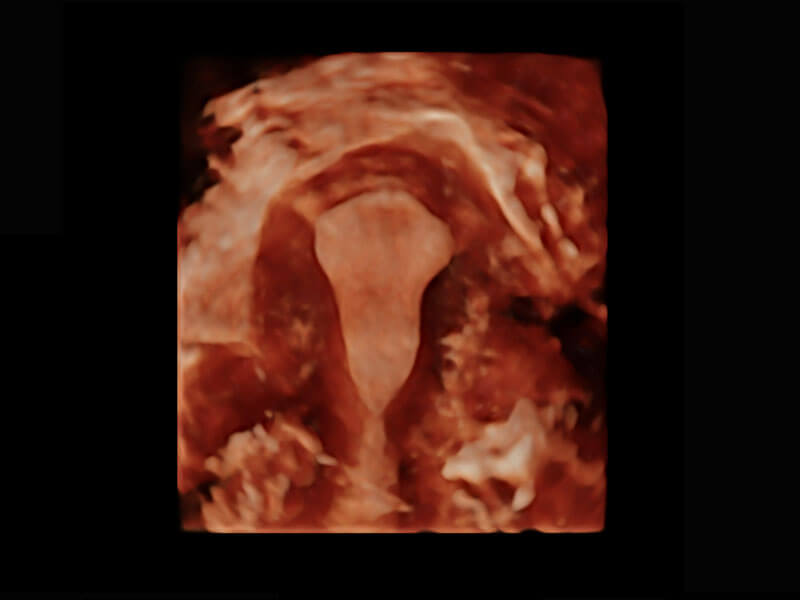

P60搭载一系列胎儿心脏成像技术,实现精细的胎儿心脏评估。

胎心容积成像